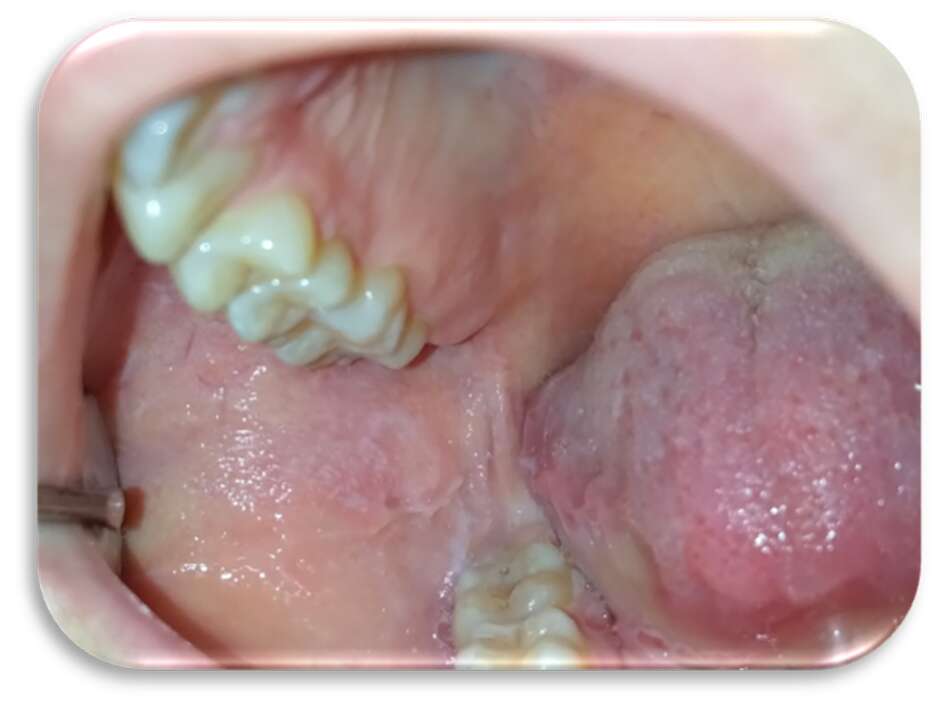

Inizialmente la paziente era stata trattata con collutorio a base di clorexidina 0,2% per circa 12 giorni senza alcun beneficio. Le lesioni si presentavano molto dolenti, erosive ed eritematose bilateralmente e simmetricamente sul ventre linguale (Figure 1 e 2) e sulla mucosa geniena, compatibili con un sospetto quadro clinico di lichen planus orale erosivo.

Sia sui margini linguali che sulle mucose geniene erano presenti, inoltre, segni di morsicatio buccarum e linea alba (Figure 3 e 4).

Al quarto giorno di applicazione, la paziente riportava un notevole miglioramento sintomatologico. A sette giorni c’era stata una regressione completa delle lesioni (Figure 5-6), con mucosa integra e normocromatica dove residuava linea alba a livello genieno e linguale (Figure 7-8), per la quale era stato consigliato alla paziente l’uso di un bite inferiore in resina morbida per evitare ulteriori traumi ai tessuti molli.